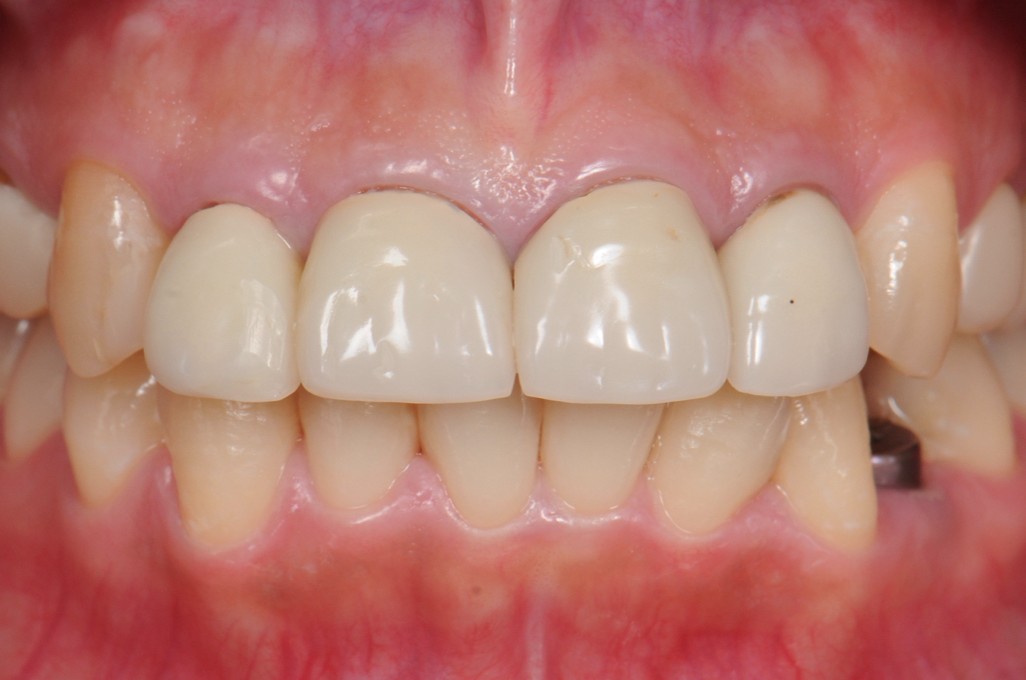

case1 症例(セラミッククラウン前歯)

治療前

治療中

治療後

| 費用(税込み) | 154,000円 |

|---|---|

| メリット・デメリット | デメリット 天然歯を削る必要がある。 |

| 治療回数 | 6ヵ月 |

| 主訴 | 前歯が黒い |